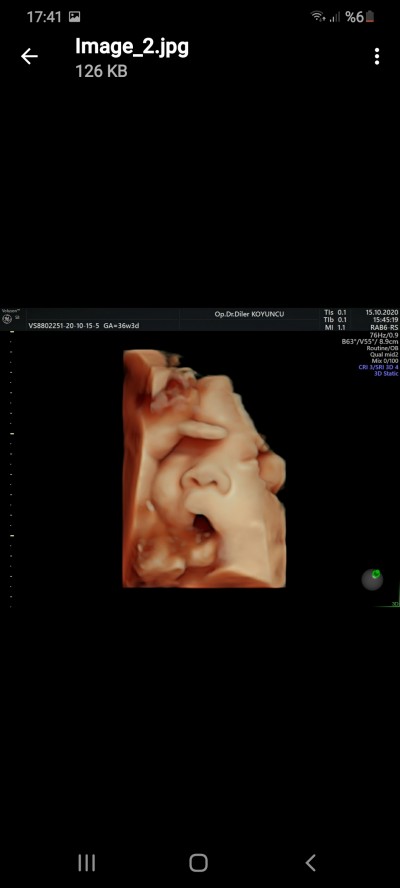

Seni kandırıyor oglum 38haftalıktı baş aşşagı çok güzel pozları var esnerken vs

image

Resmi kagıt olarak değil gmail hesabima gönderiyor doktor özel doktorsa sizde isteyin böyle renkli oldugunda gmail hesabiniza gönderir belki